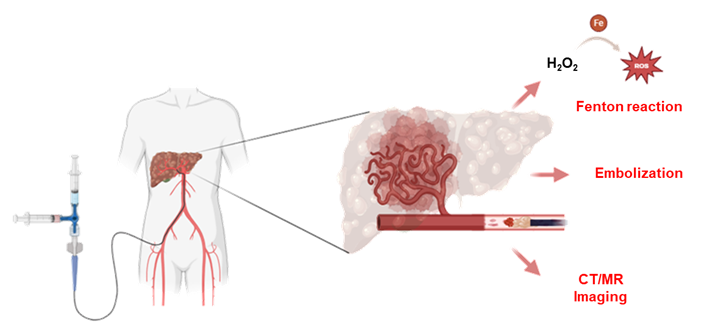

주사형 하이드로겔의 제조 및 간세포암 색전 치료 적용 개념도. |

간세포암은 전 세계적으로 발생률과 사망률이 높은 대표적인 악성 종양이다. 수술이 어려운 환자들에게는 간동맥을 찾아 항암제를 투여하고 혈류를 차단해 암세포를 사멸시키는 ‘경동맥 화학색전술(TACE)’이 중요한 치료법으로 사용되지만, 기존 색전 물질은 종양 혈관 깊숙한 부위까지 균일하게 전달되기 어렵고 시술 중 실시간 위치 확인이 어렵다는 한계가 있었다.

나건 교수 연구팀은 이를 해결하기 위해 생체적합성 고분자 기반 하이드로겔에 탄소점/철 복합체를 도입한 새로운 색전 플랫폼을 설계했다. 개발된 하이드로겔은 혈관을 물리적으로 막는 기존 역할을 넘어 ▲정밀 색전 기능 ▲CT 및 MRI 영상 추적 기능 ▲활성산소(ROS) 기반 치료 기능을 하나의 주사형 플랫폼에 통합한 것이 핵심이다.

연구팀이 마이크로카테터를 이용한 3차원 혈관 모델에서 실험한 결과, 개발된 하이드로겔은 혈관의 완전 폐색을 성공적으로 구현했다. 특히 주입 부위에 국소적으로 안정적으로 유지되어, 색전 물질이 혈류를 타고 다른 부위로 이동하는 부작용 없이 정밀한 표적 치료가 가능함을 입증했다. 이러한 우수성을 인정받아 이번 연구 성과는 재료과학 분야의 세계적 권위지인 ‘Materials Horizons (IF=10.7)’에 게재됐다.

시술 중 실시간으로 위치를 확인하며 동시에 국소 치료 반응까지 유도할 수 있어, 향후 보다 정밀한 국소 치료 기술 개발과 환자의 신체적 부담 경감에 기여할 것으로 기대된다.